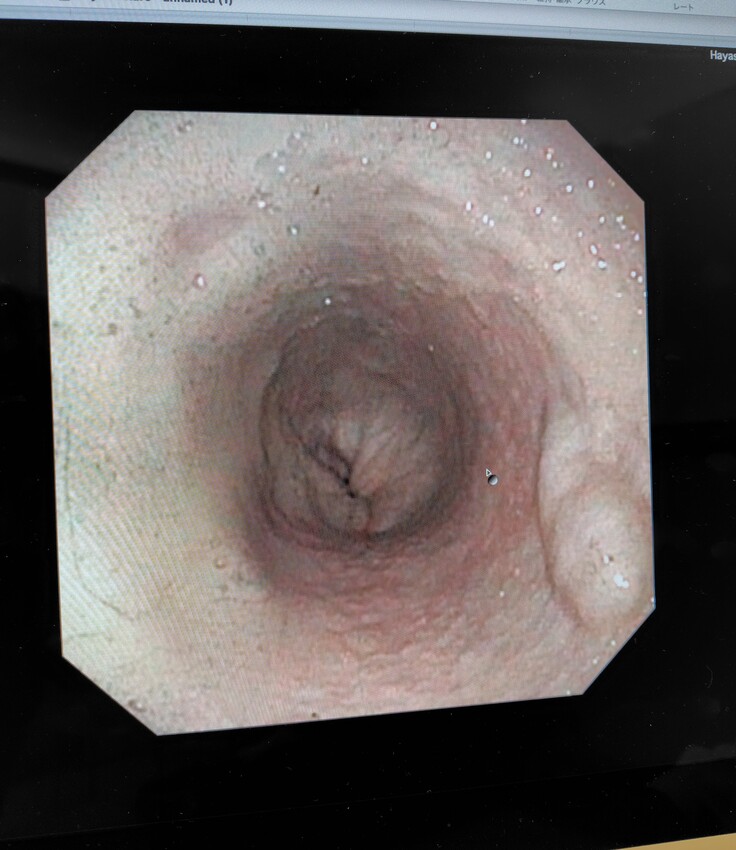

麻酔をし、内視鏡にて再度食道や胃の様子を確認され、食道の手術跡も順調に回復していたようです。胃瘻チューブの穴は医療用ボンドにて埋められそのうち塞がるとの事でした。先生に連れられて出てきてくれましたが、胃瘻チューブも取れてスッキリしてとても気分も良さそうでした😂

食道や胃もキレイな状態です😄本当に手術をしたのかなと思うくらい回復が早いです😄